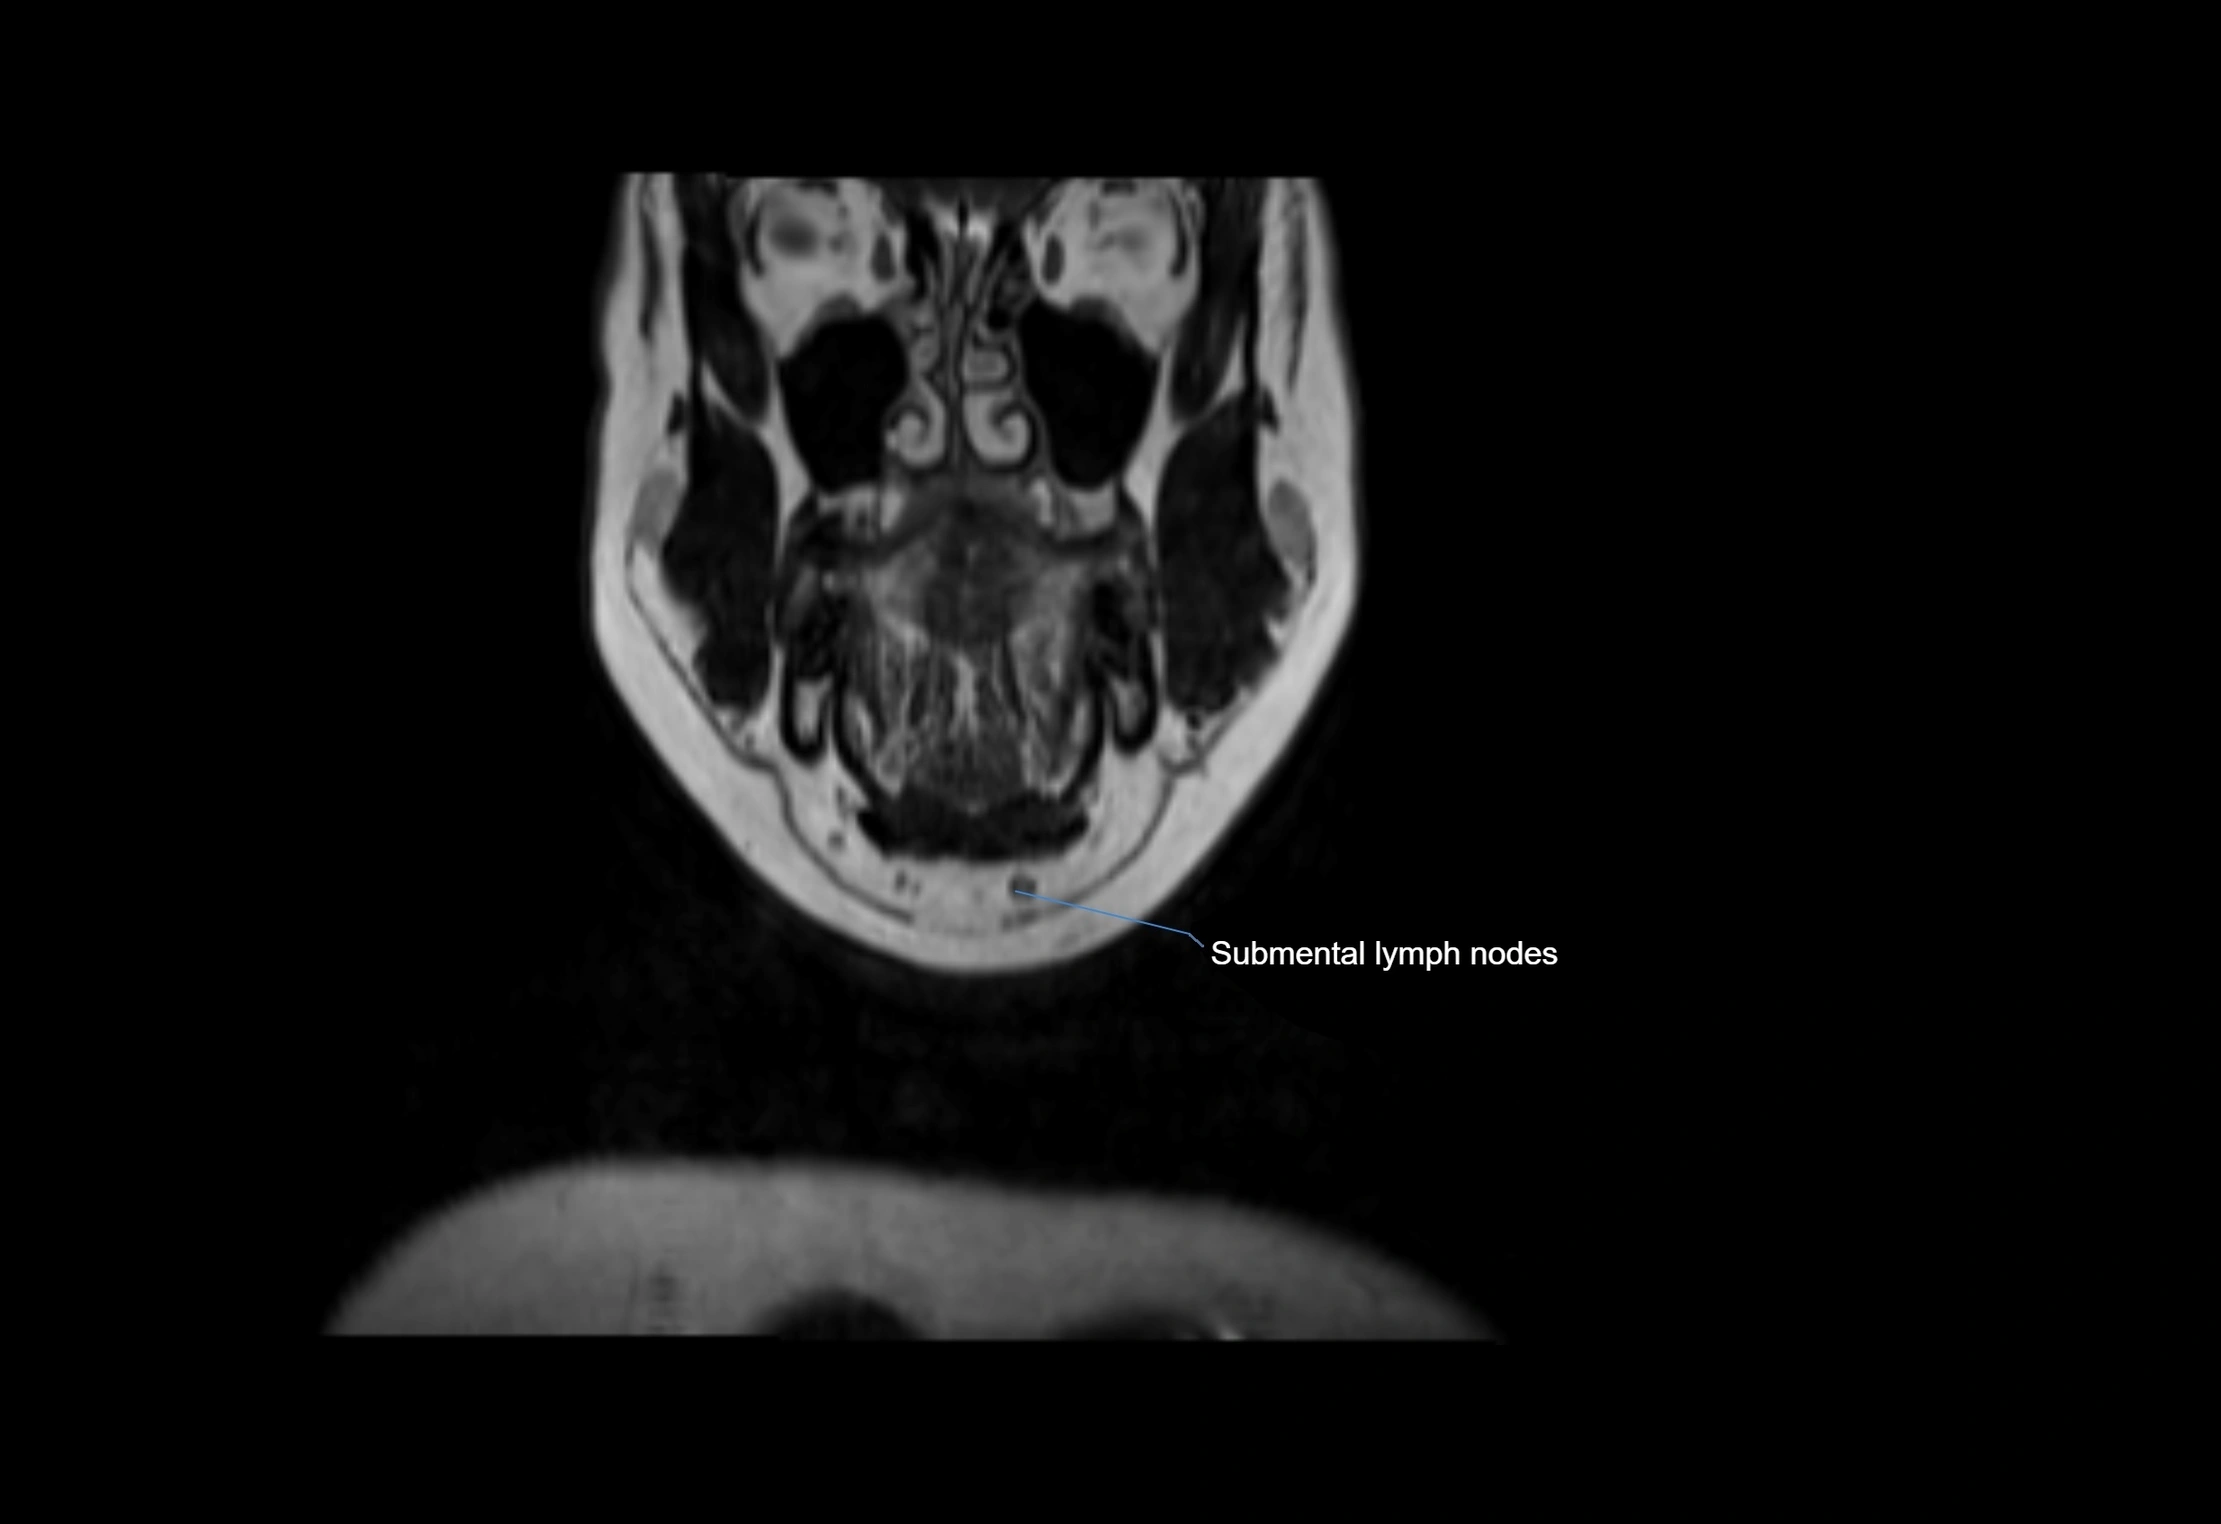

Accessory lymph nodes are small, secondary lymph nodes located along the main facial and cervical lymphatic chains, often adjacent to primary lymph nodes, such as preauricular, submandibular, or occipital nodes. They are typically less than 5 mm in diameter, embedded within subcutaneous fat or connective tissue, and may be variable in number and location. These nodes provide additional filtration and immune surveillance for lymph collected from the face, scalp, and neck regions. Accessory lymph nodes are usually non-palpable in healthy individuals but may enlarge in response to infection, inflammation, or metastasis, making them clinically significant.

• Found along primary lymph node chains, including preauricular, submandibular, parotid, and occipital regions

MRI Appearance

T1-weighted images:

• Normal accessory nodes appear as small, oval hypointense to intermediate signal structures within subcutaneous fat

• Surrounded by hyperintense fat, enhancing contrast for visualization

• Pathological nodes may appear enlarged or rounded, sometimes with cortical thickening

T2-weighted images:

• Nodes show intermediate signal, with surrounding fat bright

• Useful for detecting edema, inflammation, or infiltration

• Fatty hilum may appear slightly hyperintense relative to cortex